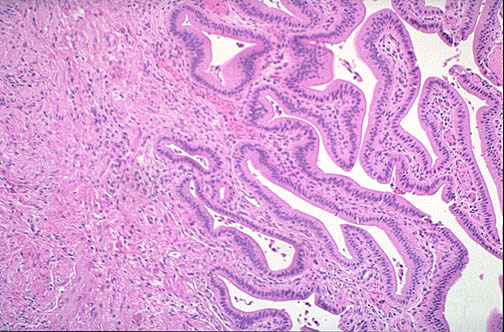

A normal gallbladder is shown here microscopically, with tall columnar cells lining mucosal folds at the right and the submucosa and the muscularis at the left.